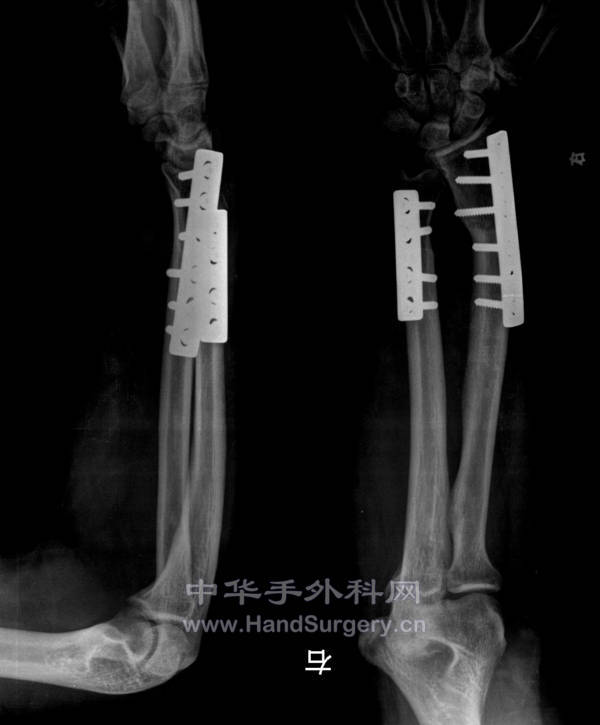

术后拍的

术后即时.jpg

骨折是钢板固定的,局部皮瓣加植皮一期完成手术,其它待二期重建。

非常漂亮的手术,学习了,骨折是用钢板固定的吗?皮肤缺损是完全植皮还是运用了局部皮瓣?是一期处理的吗?还望老师不吝赐教